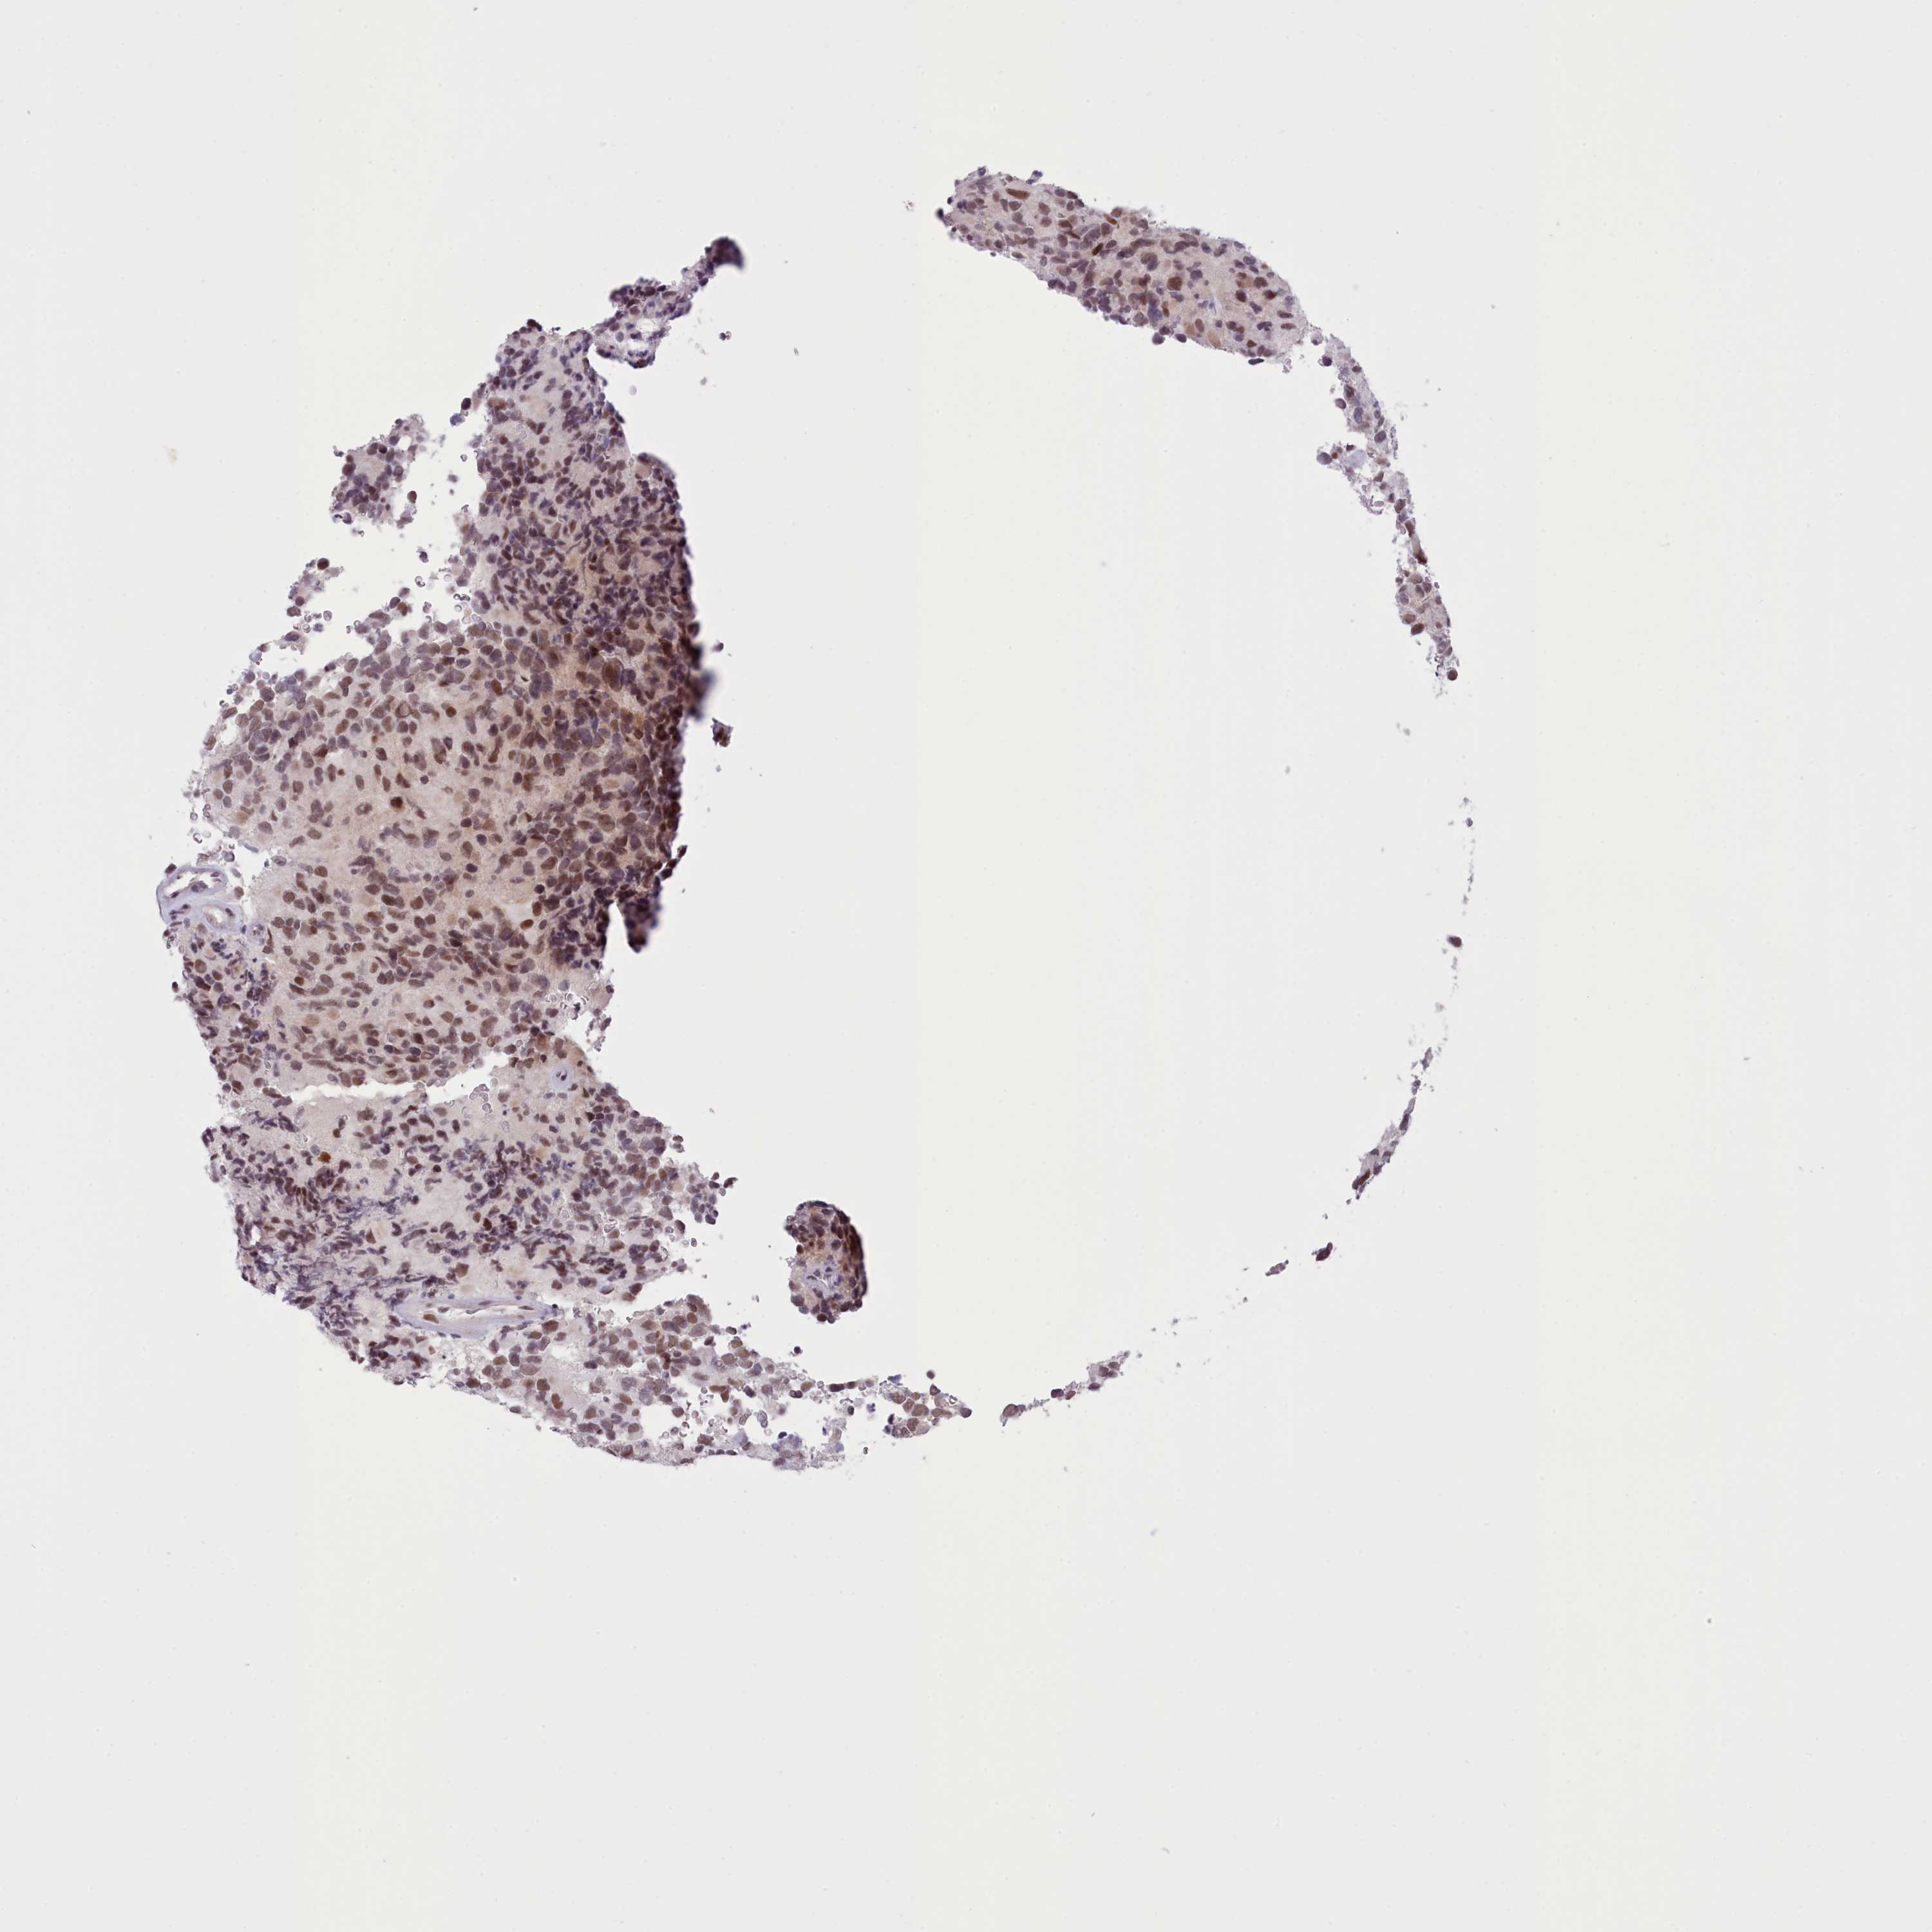

GLIOMA - Protein expressioni

A mouse-over function shows sample information and annotation data. Click on an image to view it in a full screen mode. Samples can be filtered based on level of antibody staining by selecting one or several of the following categories: high, medium, low and not detected. The assay and annotation is described here.

Note that samples used for immunohistochemistry by the Human Protein Atlas do not correspond to samples in the TCGA dataset.

Antibody stainingi

Antibody staining in the annotated cell types in the current human tissue is reported as not detected, low, medium, or high, based on conventional immunohistochemistry profiling in selected tissues. This score is based on the combination of the staining intensity and fraction of stained cells.

Each image is clickable and will lead to virtual microscopy that enables deeper exploration of all samples and also displays staining intensity scores, fraction scores and subcellular localization as well as patient and tissue information for each sample.

Antibody HPA048722

Staining

High

Medium

Low

Not detected

Intensity

Strong

Moderate

Weak

Negative

Quantity

>75%

75%-25%

<25%

None

Location

Nuclear

Cytoplasmic/membranous

Cytoplasmic/membranous,nuclear

Glioma, malignant, High grade

Glioma, malignant, Low grade